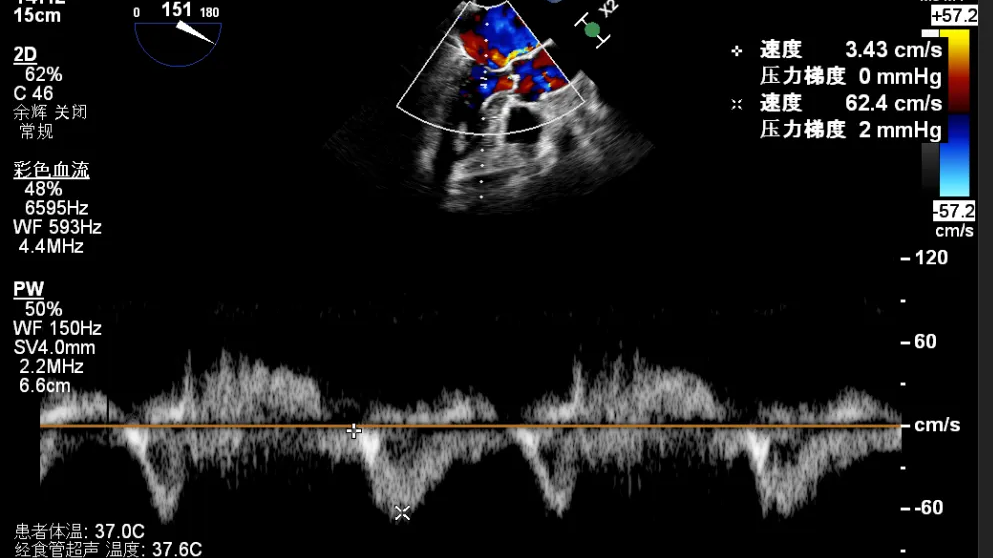

术后超声

最终在A3P2位置夹合,前叶夹合量10mm,后叶夹合量8mm,剩余瓣口面积3.45cm²,平均跨瓣压差2mmHg,反流基本消除。

全麻后,二尖瓣夹合器系统在心前区的肋间切开3-4CM小切口,暴露心脏的心尖位置,送系统送入左心房,顺利到达病变二尖瓣区域。在经食道超声辅助下,术者通过反复评估二尖瓣反流位置、抓捕位置、反流程度,首先在2偏3区位置处于二尖瓣闭合线垂直进行巧妙夹合。在2区靠近3区位置处植入了1枚ValveClamp®MVC-IIf夹,最终评估评估反流降至轻度,平均跨瓣压差降至2mmHg,手术取得圆满成功。